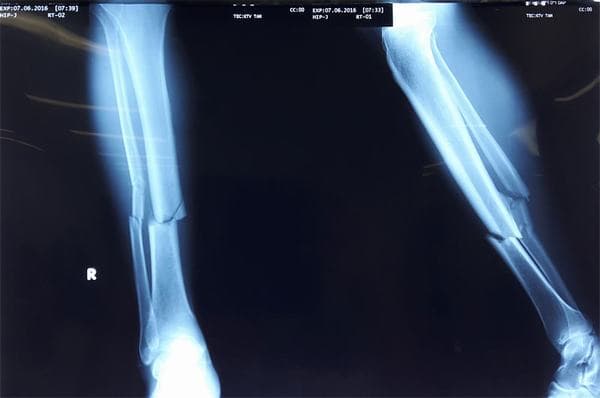

Nguyên nhân gãy xương mác và cách điều trị phù hợp

Xương mác là xương nhỏ, nằm dọc cẳng chân nên rất dễ bị gãy. Vậy nguyên nhân gãy xương mác là gì và cách điều trị như thế nào sẽ được chúng tôi giải đáp trong bài viết dưới đây.

Theo kết quả giải phẫu cơ thể người, xương mác là một đoạn xương nhỏ nhưng chắc chắn, nằm xong xong với xương ống đồng. Một đầu gắn với khớp gối, đầu còn lại là mắt cá nhân.

Xương mác có kích thước nhỏ, mảnh nên rất dễ bị gãy khi có áp lực lớn tác động vào xương nhiều hơn so với sức tải của nó. Nguyên nhân xương mác bị gãy thường gặp như:

Gãy xương cần phải được xử trí đúng cách để tránh biến chứng

Tuy nhiên khi bị gãy xương mác, người bệnh cần được sơ cứu và xử trí đúng cách để tránh biến chứng, ảnh hưởng xấu tới chức năng vận động của cơ thể.